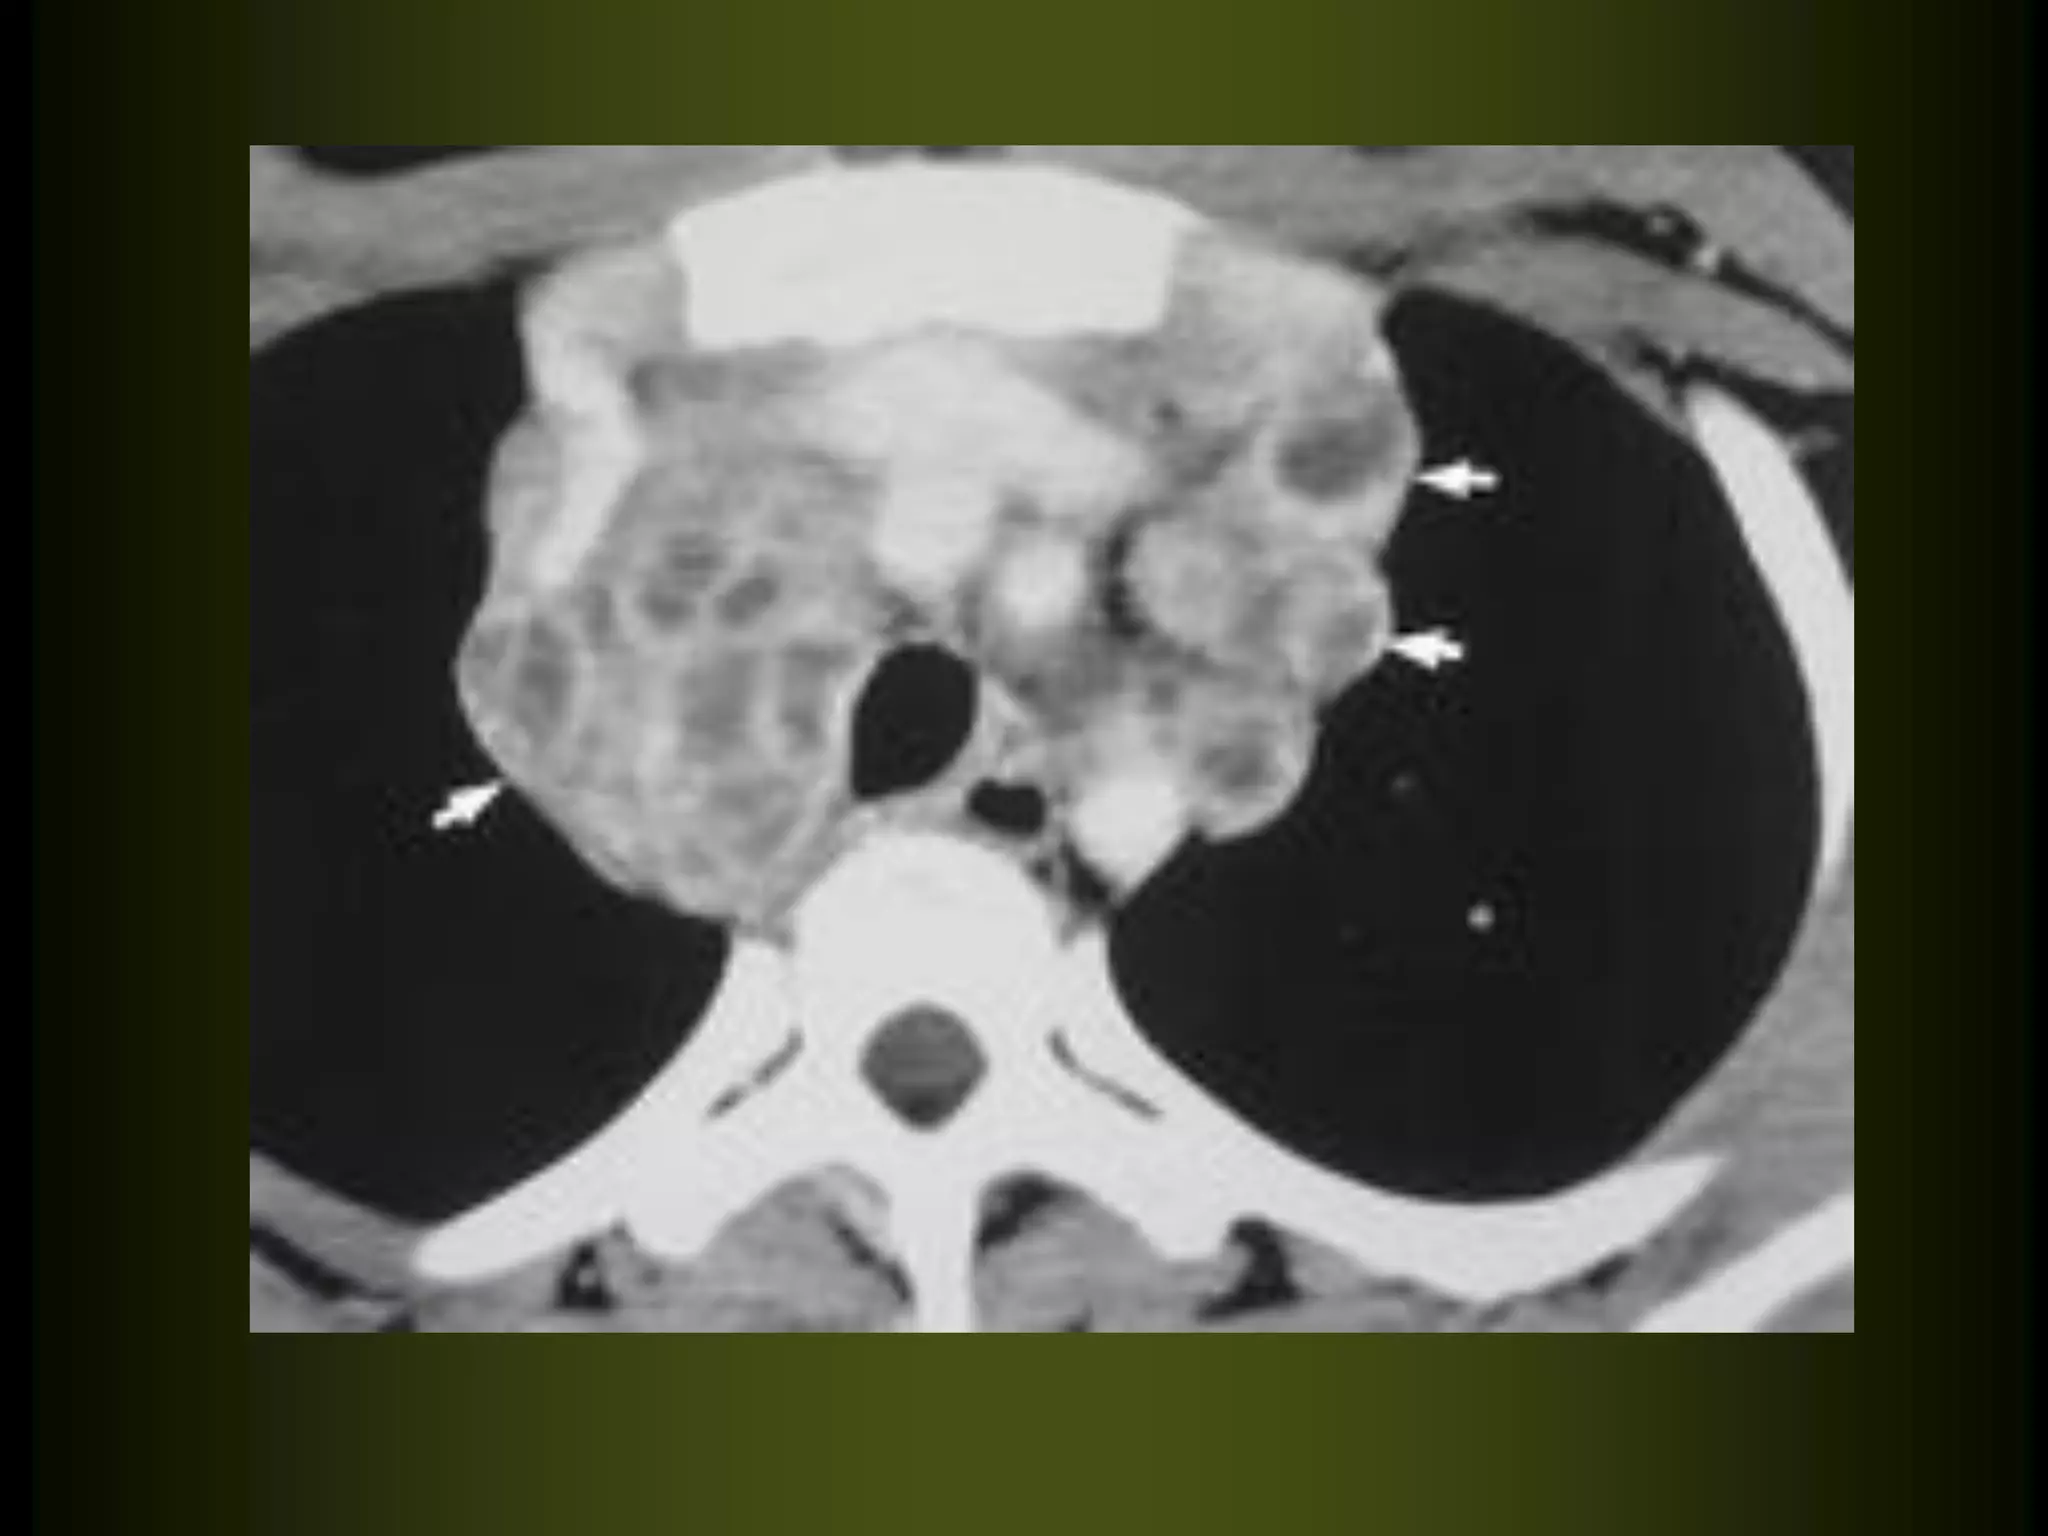

Multiple cysts of metastasis

from

squamous

cell

carcinoma.